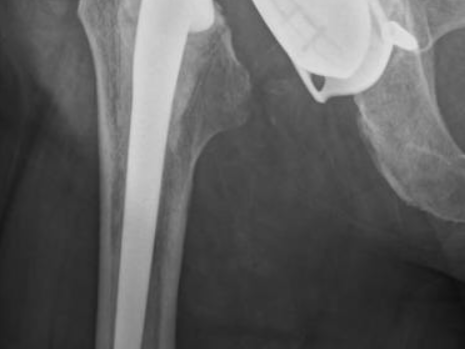

Cas 1. Luxation fémoro-acétabulaire de PTH

Les luxations de PTH sont des urgences chirurgicales surtout si elles surviennent dans les trois premiers mois. L’interrogatoire détermine les circonstances de la luxation et le délai entre la pose de la prothèse et la luxation. Les radiographies de hanche confirment le diagnostic et vérifient l’absence de fracture péri-prothétique. En cas de doute, un scanner de hanche peut être prescris.

La réduction doit se faire au bloc opératoire sous anesthésie générale. Des radiographies per-opératoires permettent de vérifier la bonne réduction des implants et l’absence de déplacement secondaire de la prothèse. Des manœuvres sous scopie vérifient la stabilité des implants. Une fois réduite, le membre inférieur luxé est immobilisé par une attelle de genou pendant 3 semaines afin d’éviter les rotations de la hanche, qui sont une source de luxation.